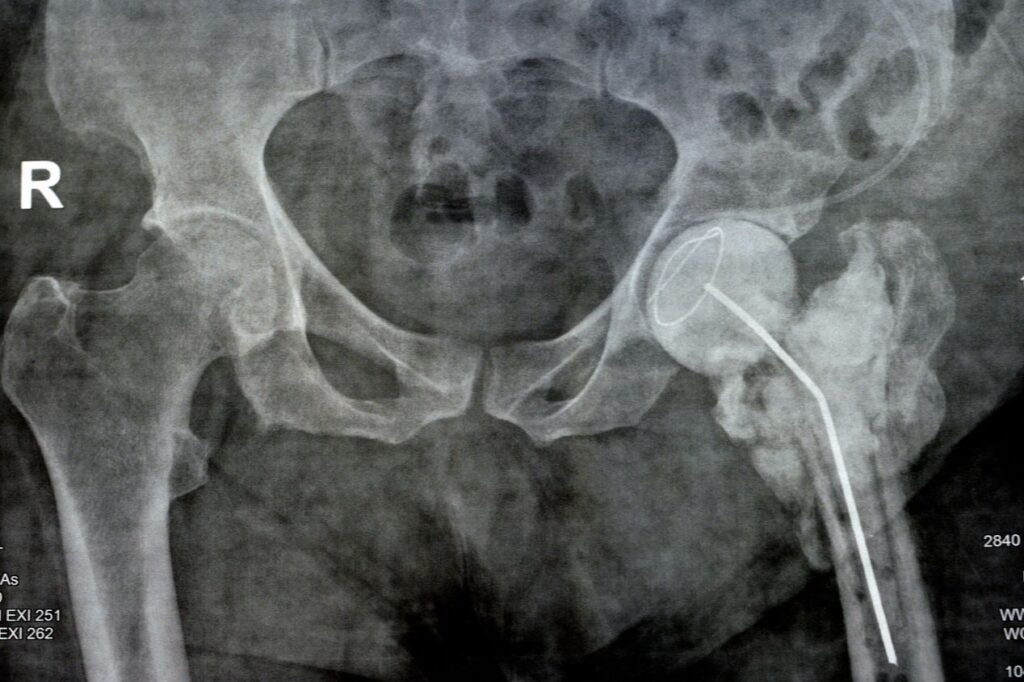

Αποκατάσταση μετά από κάταγμα ισχίου

1. Χειρουργική επέμβαση ή συντηρητική αγωγή: Ανάλογα με την έκταση του κατάγματος, μπορεί να απαιτηθεί χειρουργική επέμβαση ή συντηρητική αγωγή, όπως η απλή ανάπαυση ή η χρήση αναπηρικού καροτσιού. Η χειρουργική επέμβαση είναι απαραίτητη στο 95% των περιπτώσεων καταγμάτων ισχίου.